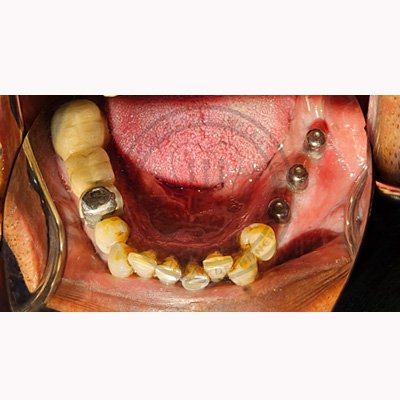

Case – 11 Baleram